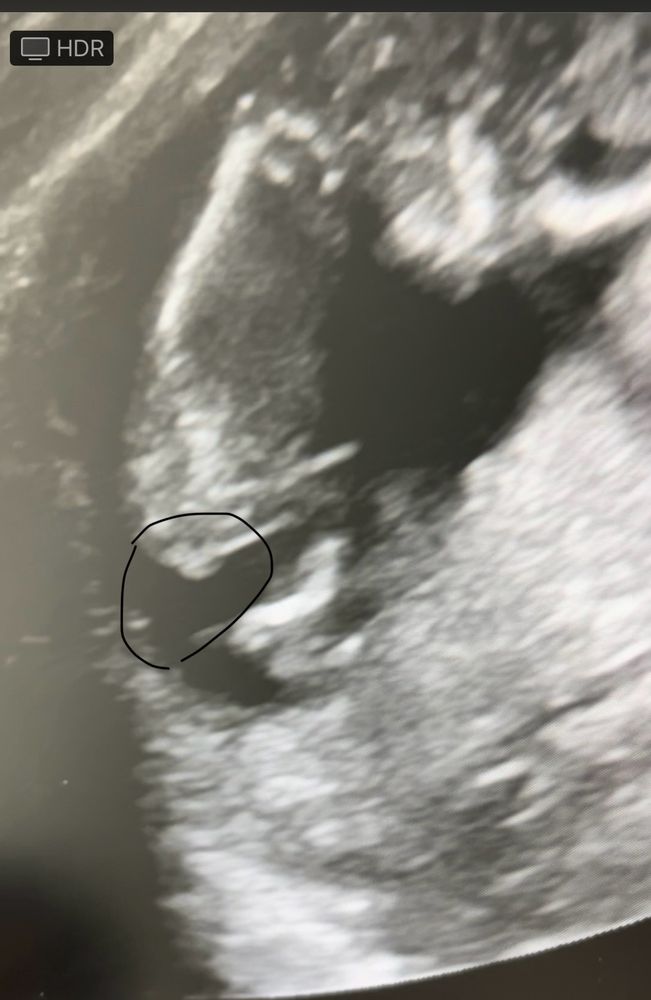

Девочки а здесь видно кто?

в этом сроке еще непонятно. Через пару недель под нг на определение Пола по узи запишитесь и там будет видно, орган половой сформируется

Рано и ракурс плохой,как на кофейной гуще гадать.

Не тот ракурс

Тут у вас ничего не понятно. Дождитесь 20 недели, там уже могут сказать, так как сформируются уже половые органы, если ребёнок повернётся как надо, если не в терпеж сдайте кровь

Lesya, 14.2 кому то и в 11 недель говорят :(